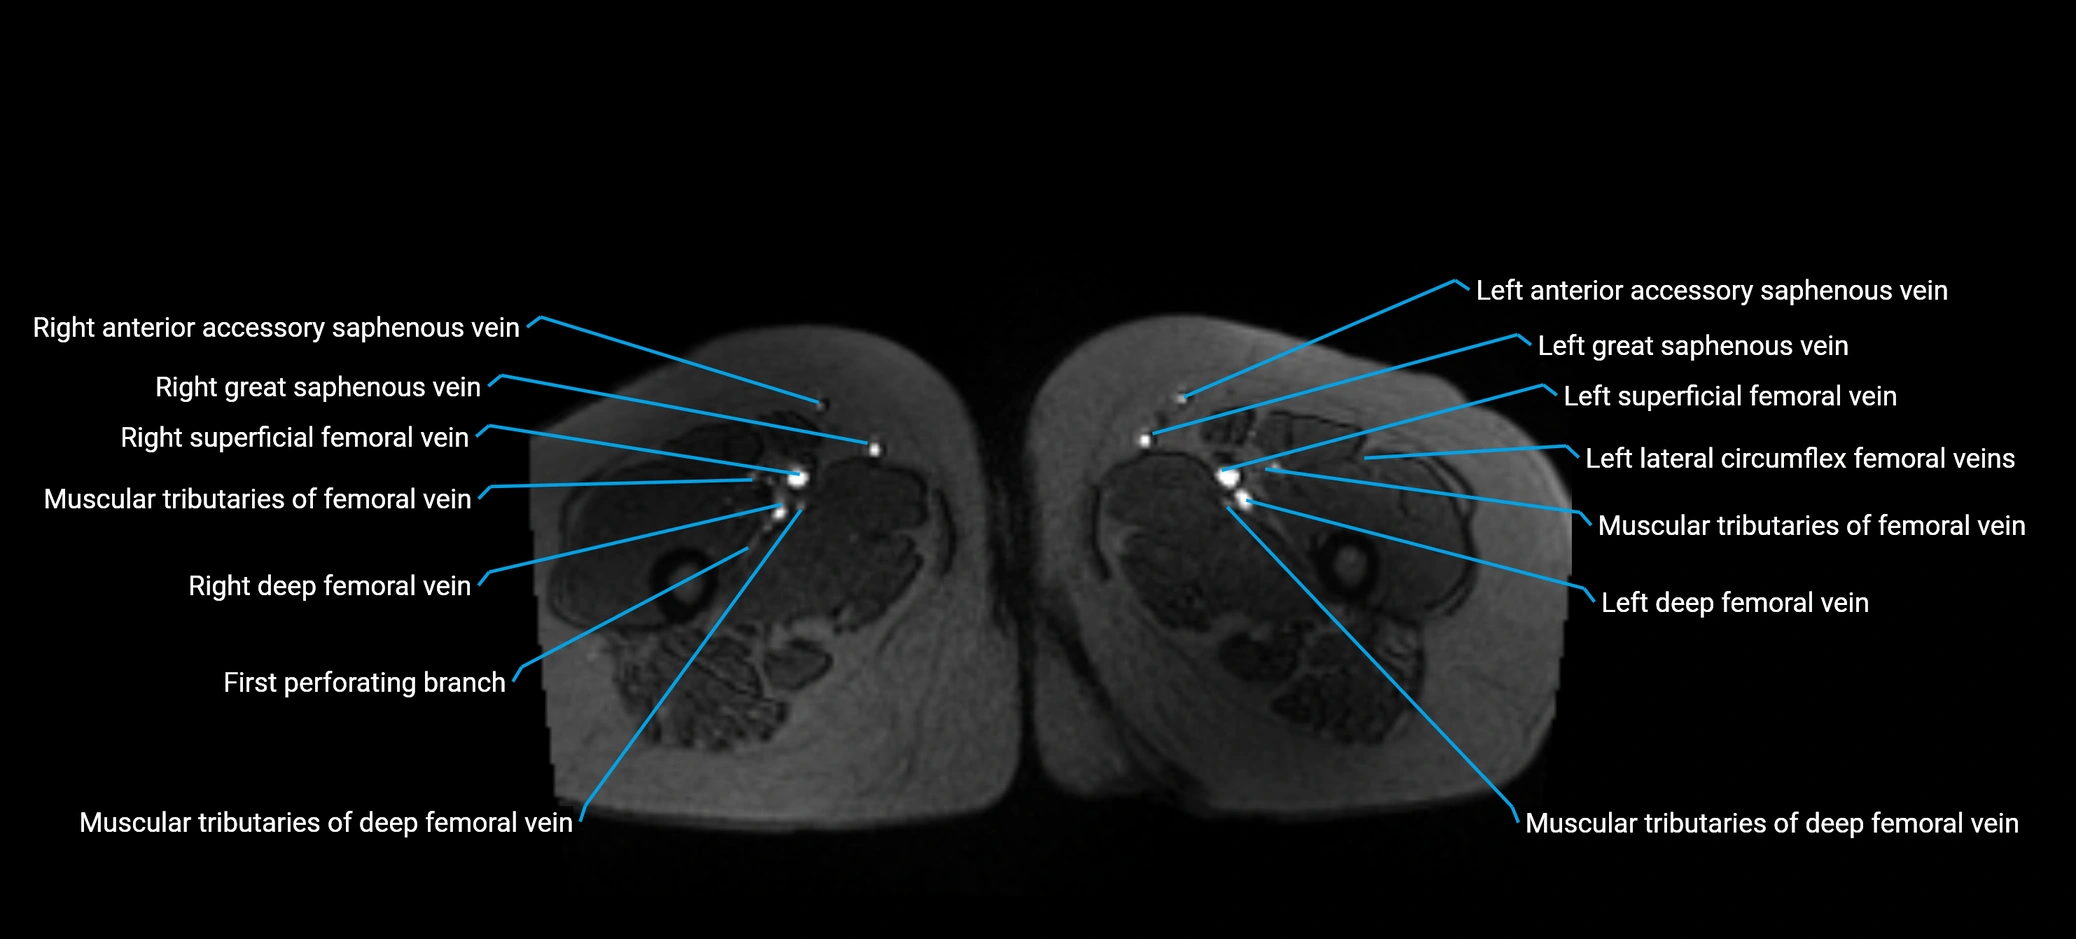

MRI image

image